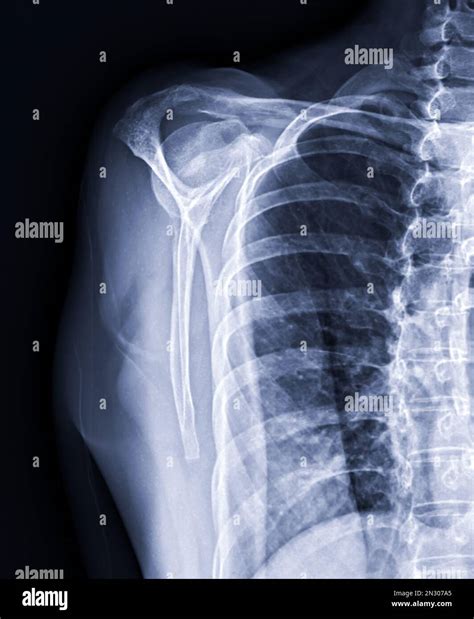

Common Conditions Diagnosed with X Ray Shoulder Joint

X-rays are a primary diagnostic tool for various shoulder conditions. Some of the most common conditions that can be identified through an X Ray Shoulder Joint include:

• Fractures: Breaks in the bones of the shoulder, such as the humerus, scapula, or clavicle.

• Dislocations: When the head of the humerus is forced out of the shoulder socket.

• Arthritis: Inflammation and degeneration of the joint, which can be either osteoarthritis or rheumatoid arthritis.

• Rotator Cuff Tears: Injuries to the tendons and muscles that stabilize the shoulder joint.

• Bone Spurs: Abnormal bone growths that can cause pain and limit movement.